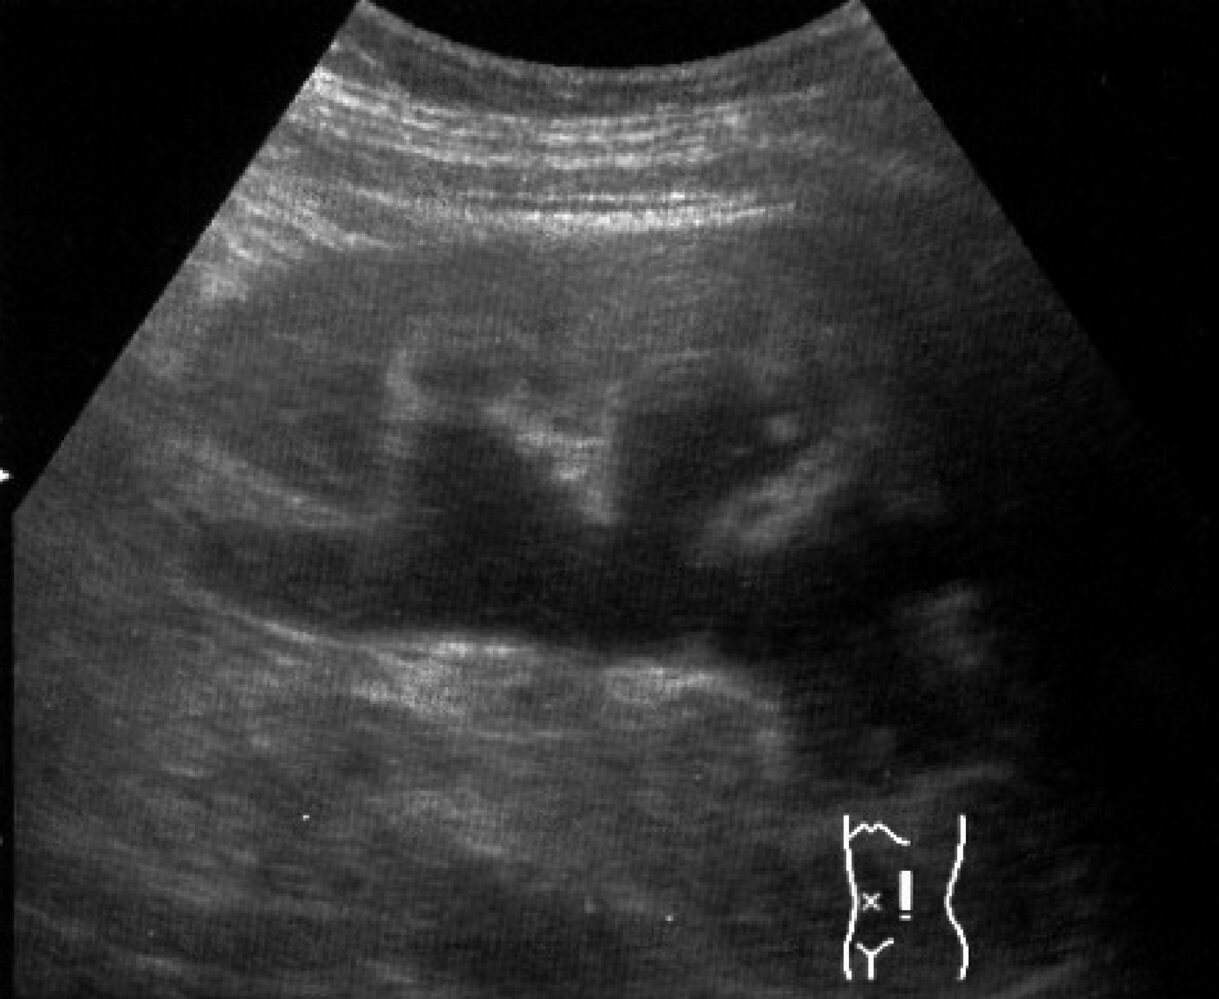

Renal bladder ultrasound (RBUS) [2][3][5][14]

• Preferred initial imaging modality for pediatric UTIs [3][14]

• Most structural abnormalities can be detected on RBUS.

• Does not expose the patient to radiation

• Potential findings include:

• Acute complications of pediatric UTI

• Congenital anomalies of the kidneys

• Secondary signs of vesicoureteral reflux (VUR) [2][3]

• Abdominal masses affecting the urinary system

• Renal parenchyma changes (not sensitive)